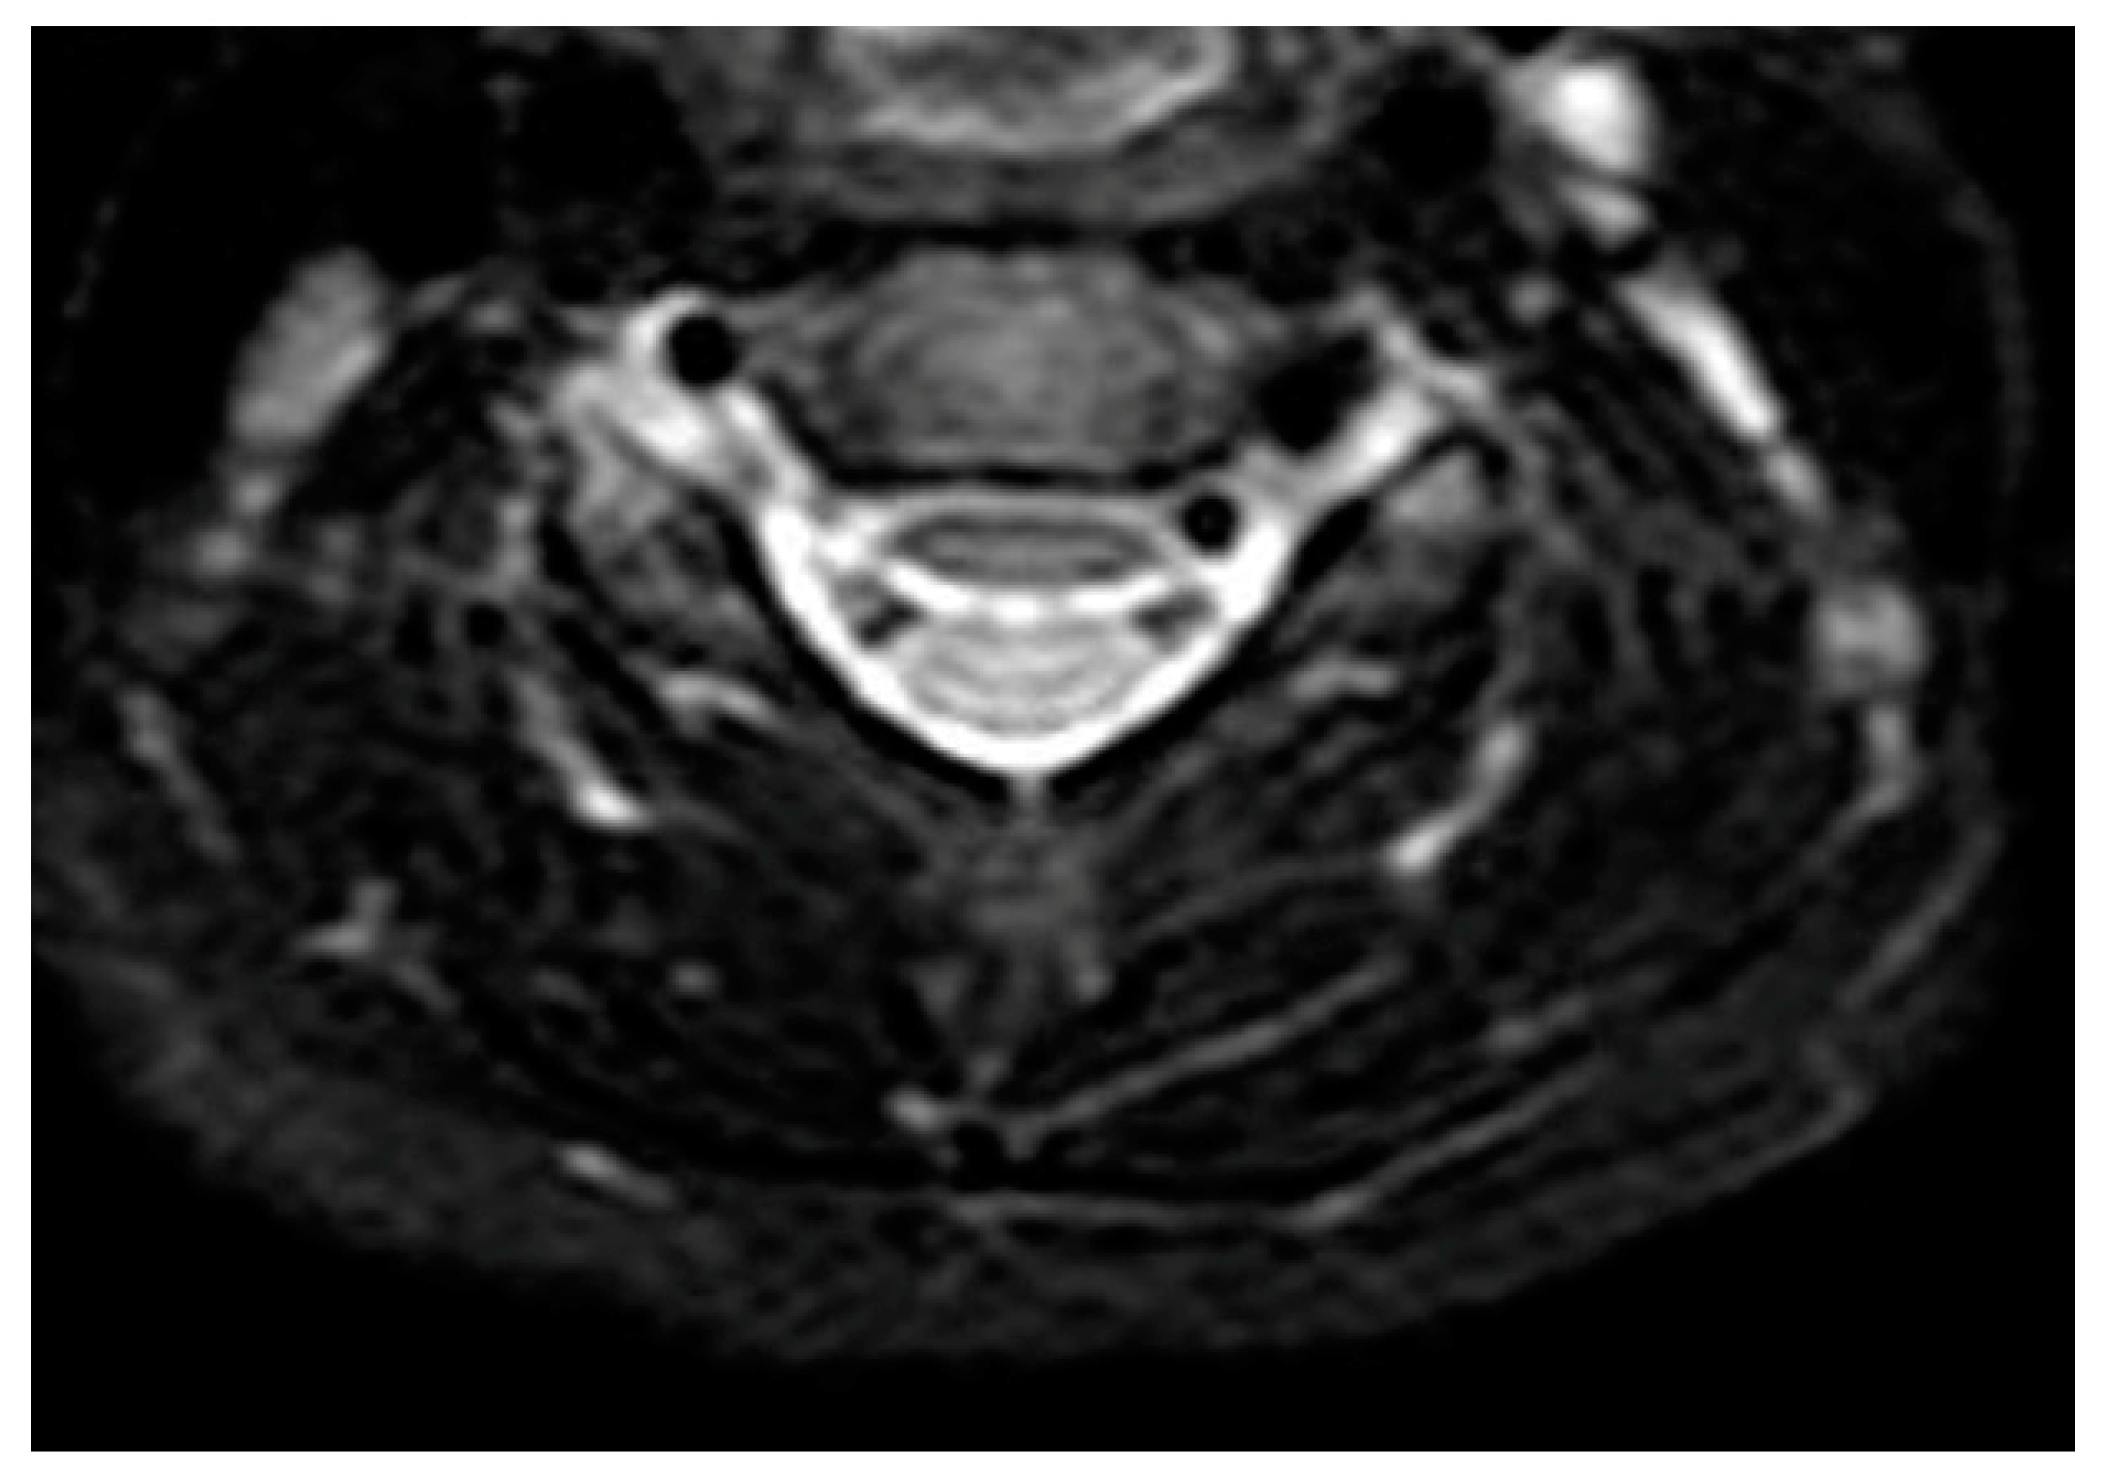

2.2. Investigations for Recurrent Neck Abscesses